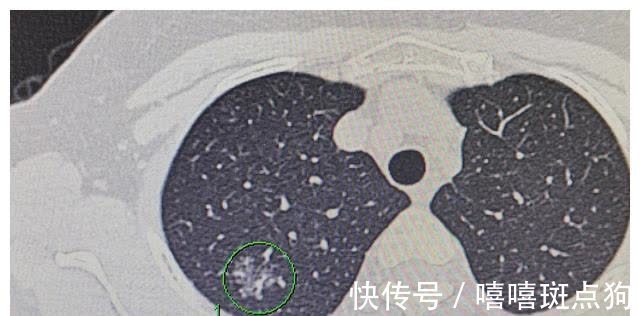

今天分享的这三例磨玻璃结节型肺腺癌都是上周手术的,结节图像和病理报告如下。图1和2的肺磨玻璃结节居然是胶样癌,分化程度低,这是我第一次碰到。图3-6是黏液腺癌,在以前的磨玻璃手术中也多次碰到,包括黏液原位腺癌,黏液微浸润腺癌和浸润性黏液腺癌都碰到过。

我以前的肺磨玻璃结节手术中,肺腺癌的10余个亚型几乎都碰到过。磨玻璃结节型肺癌,开始阶段一般以贴壁生长的肿瘤细胞起步,这是高分化的,恶性程度低。逐渐出现浸润灶到浸润成分占主体,如腺泡为主型和乳头为主型,这一般是中分化的。也可以演变成实体亚型、微乳头亚型,黏液亚型,胶样腺癌等等,这些是低分化的,恶性程度较高。